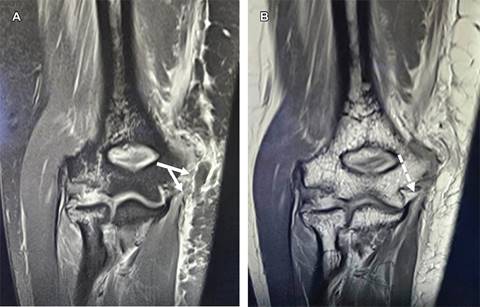

Figura 2: Imágenes de resonancia magnética de codo en corte coronal en vista anterior, se muestra en (A) desinserción tendinosa de los tendones laminares del pronador redondo, palmar mayor y palmar menor ( flechas en Y ); en (B) fractura avulsión del epicóndilo medial con tendinopatía traumática del tendón del flexor común superficial (flecha punteada).